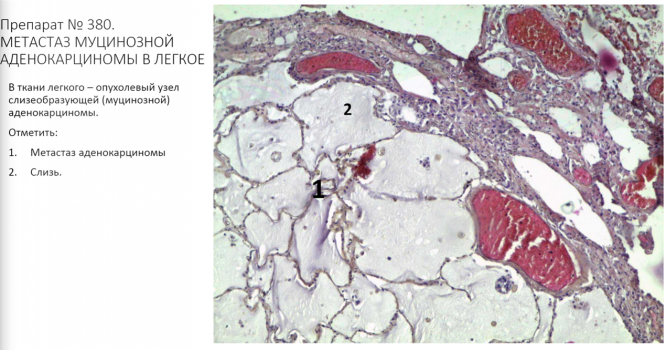

Для студентов СГМУ по предмету Патологическая анатомияМикропрепараты к практическому занятию. Учение об опухолях. Эпителиальные опухолиМикропрепараты к практическому занятию. Учение об опухолях. Эпителиальные опухоли